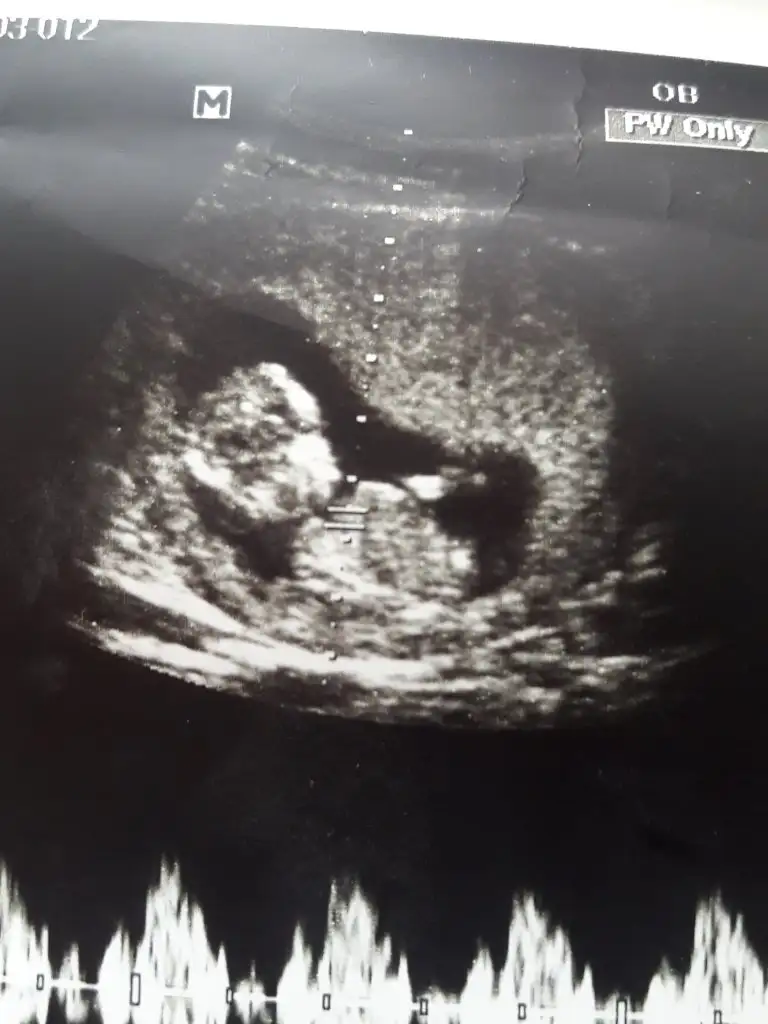

merhaba dün 2 farklı yerde ultrason çektirdik ama cinsiyetini öneremedik rica etsem usg bakıp tahmininizi söyliyebilirmisiniz 16. haftayıda geçtik hayırlısıyla teşekkkürler.

merhaba dün 2 farklı yerde ultrason çektirdik ama cinsiyetini öneremedik rica etsem usg bakıp tahmininizi söyliyebilirmisiniz 16. haftayıda geçtik hayırlısıyla teşekkkürler.Eki Görüntüle 2309422